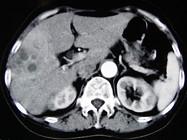

问题 女,66岁,右上腹痛,发热伴有黄疸两月余,消瘦、纳差,影像检查如图,最可能的诊断是()

选项 A.胆囊结石及脂肪肝 B.胆囊结石及肝血管瘤 C.胆囊癌肝转移 D.肝内胆管细胞癌 E.胆囊癌及原发性肝癌

答案 C